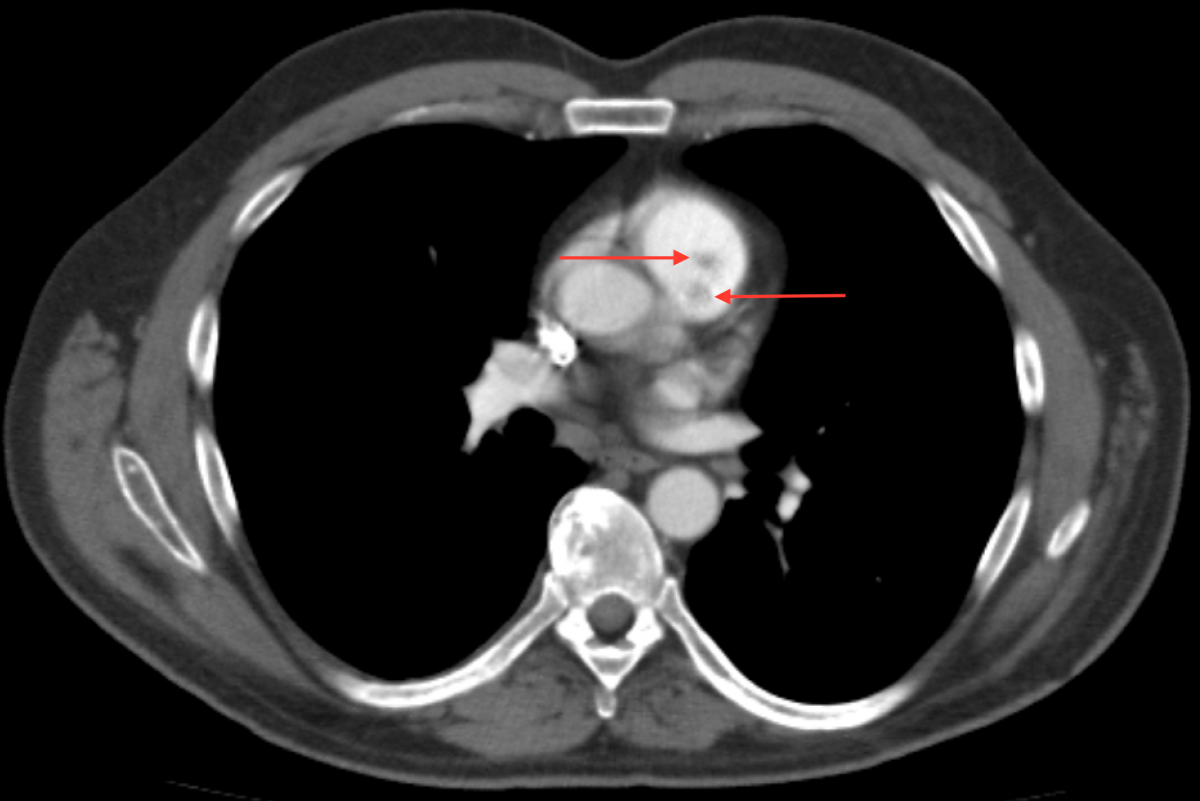

A 56-year-old Caucasian male presented with exertional dyspnea, occasional palpitations, and night sweats. He underwent transthoracic echocardiography, which suggested a possible pulmonic valve tumor. A follow-up transesophageal echocardiography demonstrated a freely mobile, well circumscribed, nearly 1 cm tumor on the anterior leaflet of an otherwise structurally normal pulmonic valve (Figure 1). Contrast chest CT was remarkable for bilobulated tumor of the pulmonic valve consistent with a PFE (Figure 2).